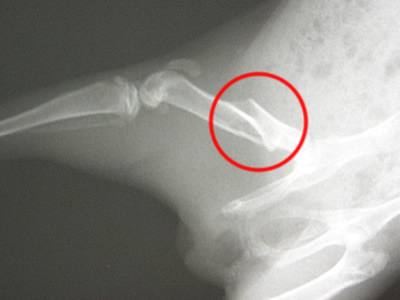

- Röntgenbild eines Oberschenkelbruchs

Goldy war 5 Wochen alt, als sie sich den Oberschenkel brach. Vermutlich war sie an einer Weidenbrücke hängen geblieben. Einige Tierärzte raten in so einem Fall zur Einschläferung. Das ist in der Regel aber nicht nötig und nur ein wirtschaftliches Argument. Goldys Bruch verheilte gut, in dem sie relativ ruhig gestellt wurde. Sie wohnte 5 Wochen in einem Hamsterkäfig. Zur Linderung der Schmerzen kann ein Schmerzmittel gegeben werden. Ab und an kann man am Gang noch sehen, dass sie an diesem Bein verletzt war. Goldys Bruch heilte aus.